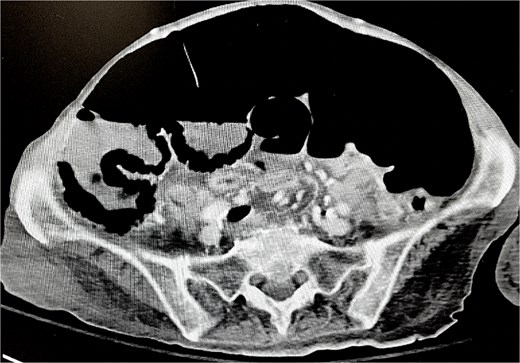

Soon thereafter, a large prolapse of the cecostomy site was noted (Figs 2 and 3). Conservative measures including manual reduction and hyperosmotic agents were unsuccessful. On April 15, 2025, she was taken to the operating room. Diagnostic laparoscopy revealed a small fascial defect at the cecostomy site with cecal intussusception. The fascial defect was extended cephalad, and the prolapsed cecum was successfully everted and reduced (Fig. 4). Due to the chronically dilated right colon and the patient’s history of refractory ACPO, a right hemicolectomy with end-ileostomy was performed.

Successful eversion and reduction of cecostomy intussusception.